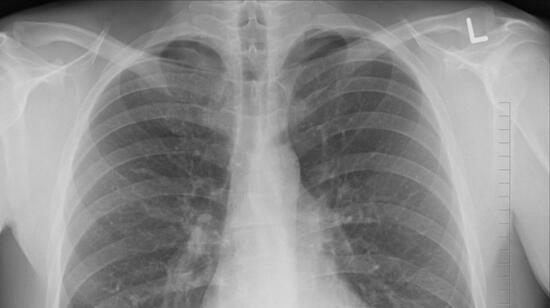

Pulmonology Myths Debunked: Common Misconceptions About Lung Health

Maintaining good lung health is crucial for overall well-being, yet many misconceptions surround pulmonary diseases like COPD, asthma, and lung cancer. In this blog, we debunk common myths about lung health and provide accurate information to help you better understand and protect your ...

Respiratory diseases are the most common cause to visit doctors in India, especially Asthma and COPD, which have wide variations in morbidity and mortality in various geographic locations. India has the 4thlargest cases of asthma in the world but leads in the most number of asthma patient death ...